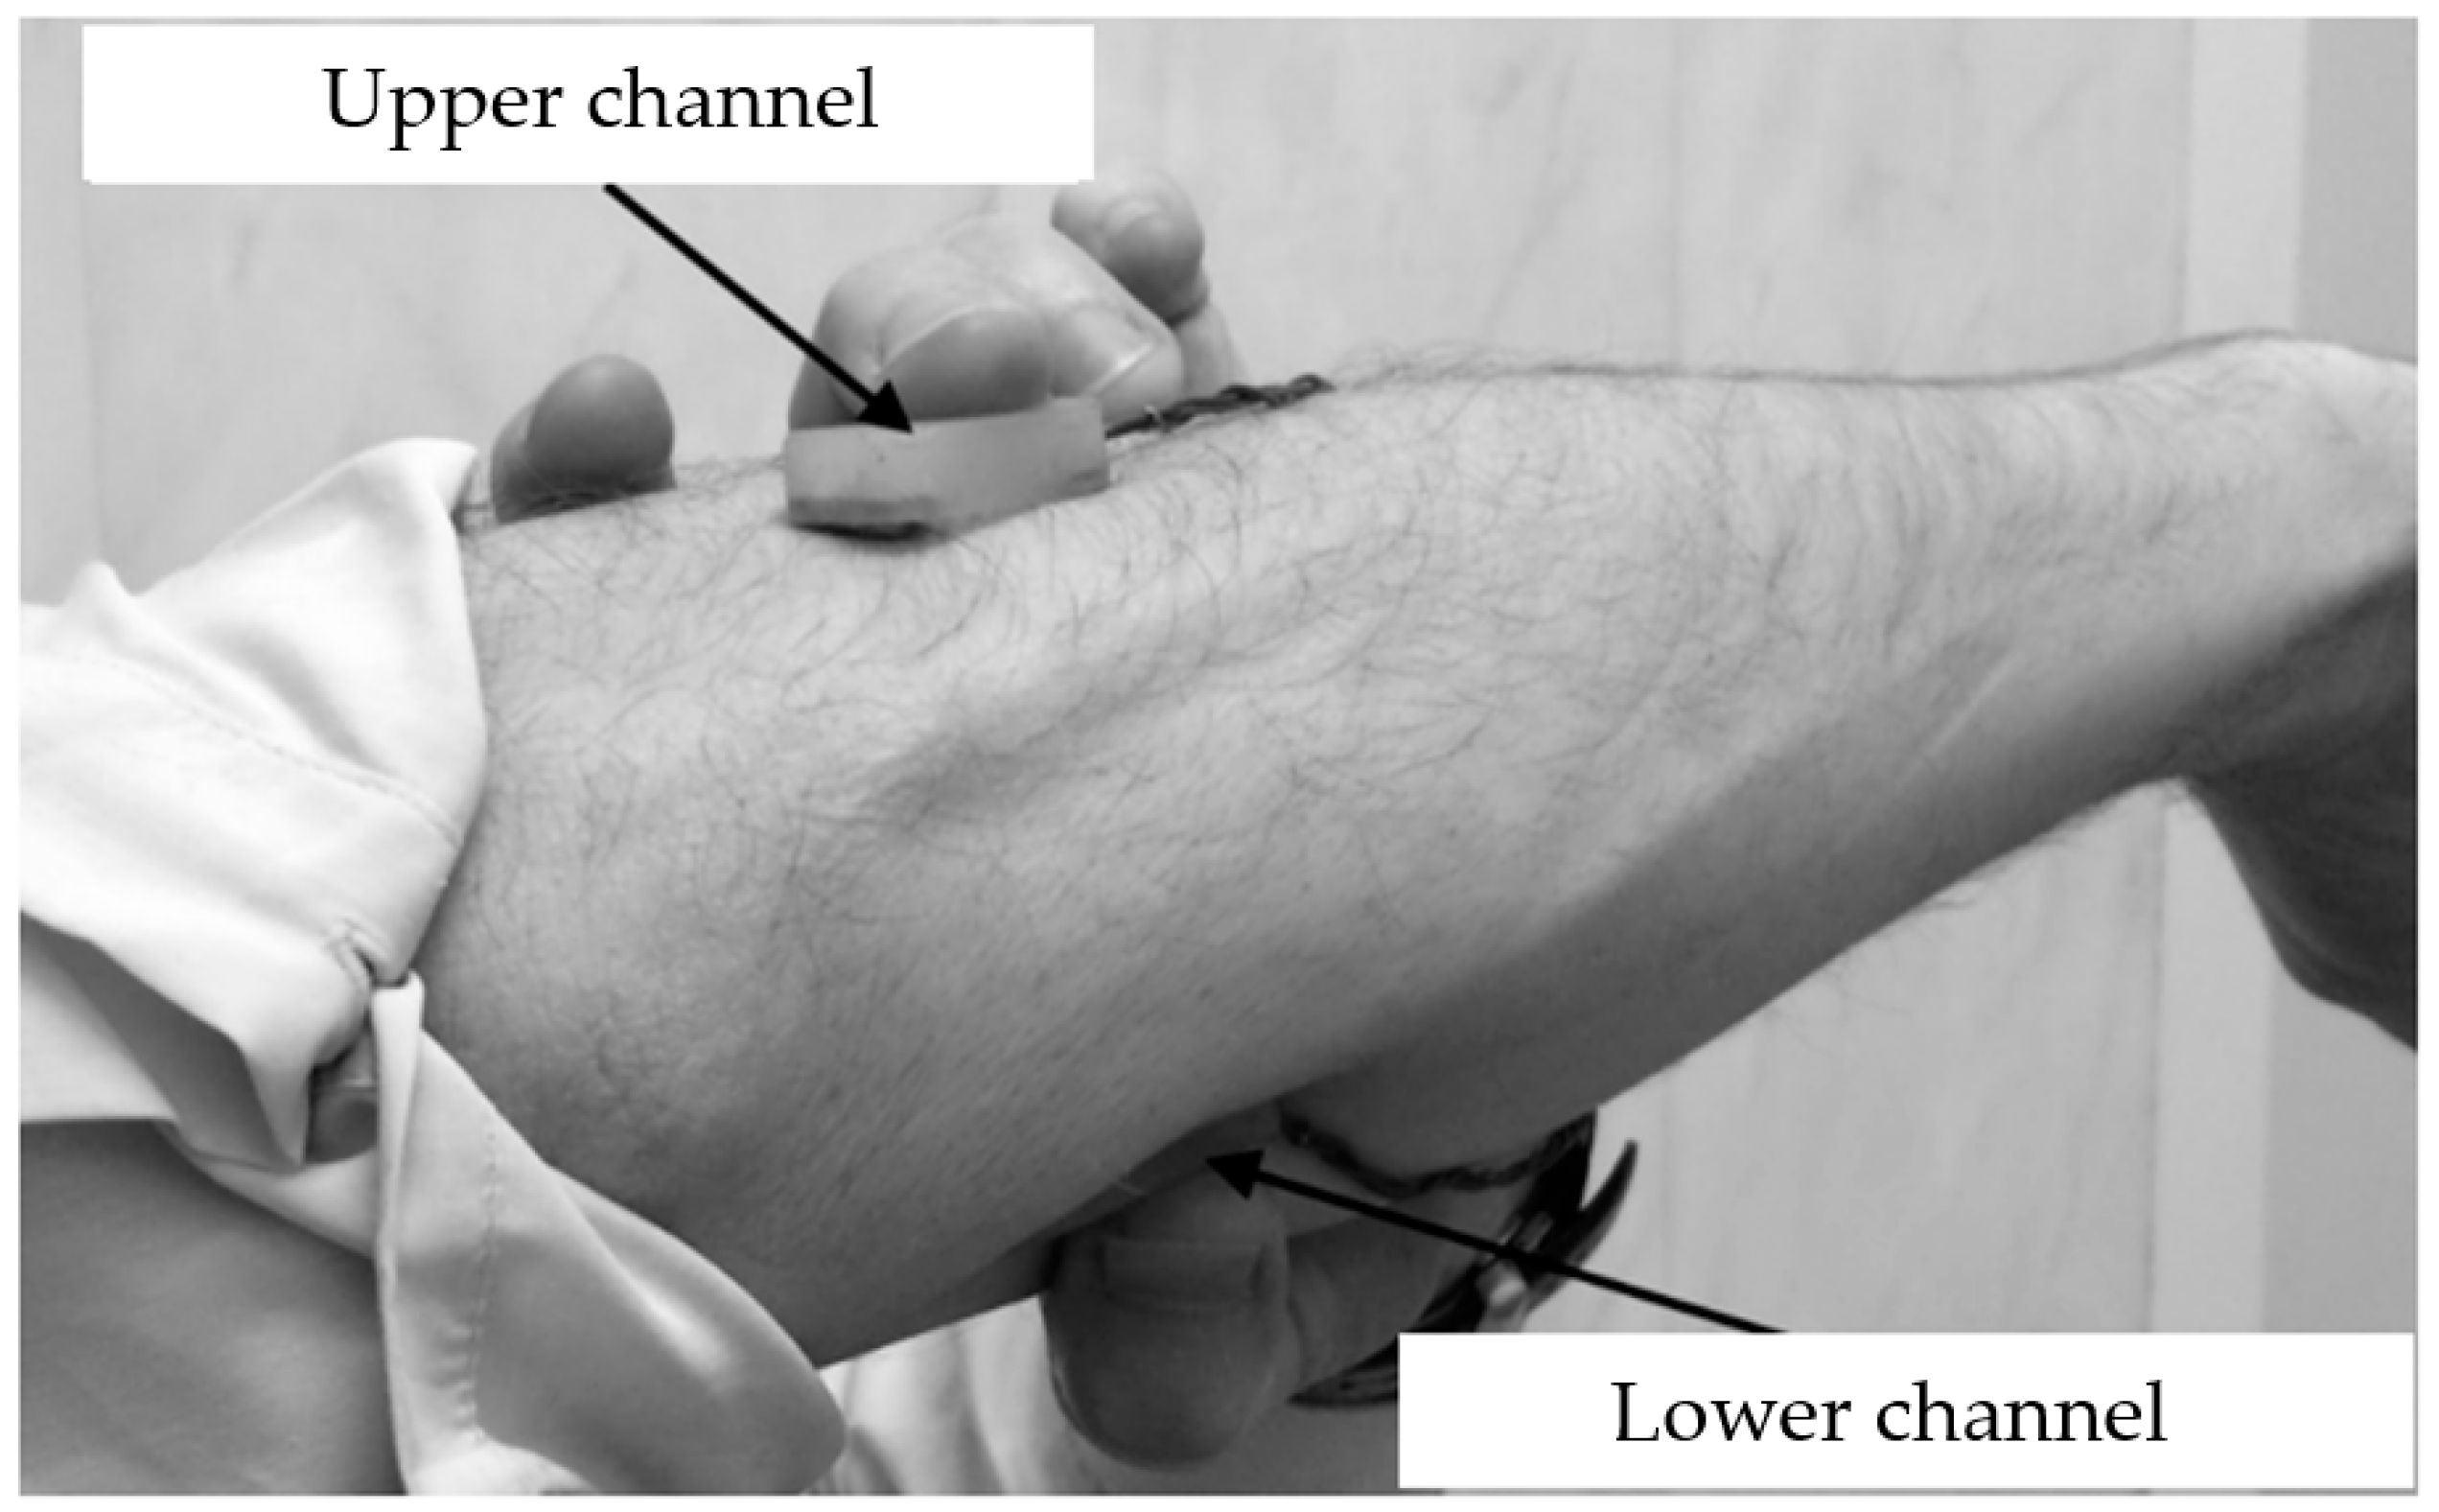

2.6. Measurement Design

3.2. Study of the Amplitude Parameters of the Electrical Impedance Myography Signal at Different Pressures of the Electrode System